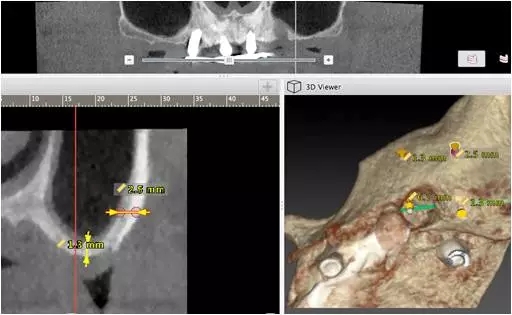

10個月后出現左上頜咬合痛,X線檢查發現上頜左側前磨牙區傾斜種植體周圍低密度影,臨床檢查種植體松動,其余種植體骨結合良好,遂拔除該種植體(圖3-4)。愈合3個月,CBCT片顯示:25區種植窩空虛(圖5),愈合不佳,26區竇底剩余骨高度不足2mm(圖6),其余種植體骨愈合良好,15區傾斜種植體邊緣骨疑似吸收至第三螺紋(結合全景片)。患者要求固定修復。

圖5

圖6